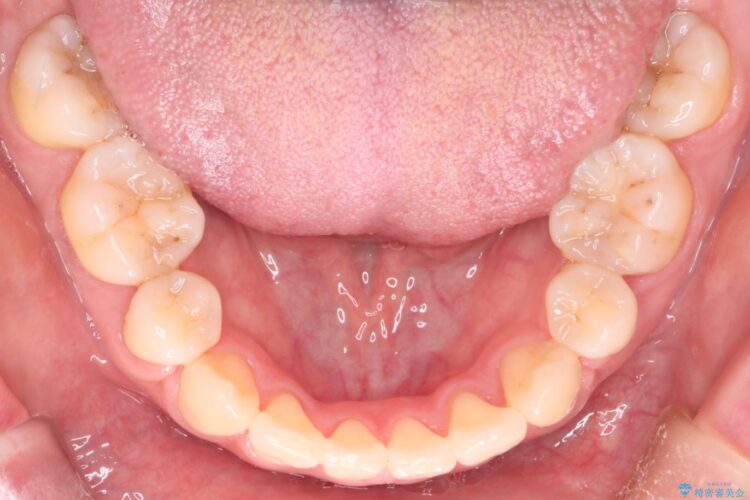

上の前歯のデコボコを主訴にご来院された患者様です。

重度の叢生が認められたため、上下左右4番目の歯を抜歯しワイヤー矯正治療を行いました。